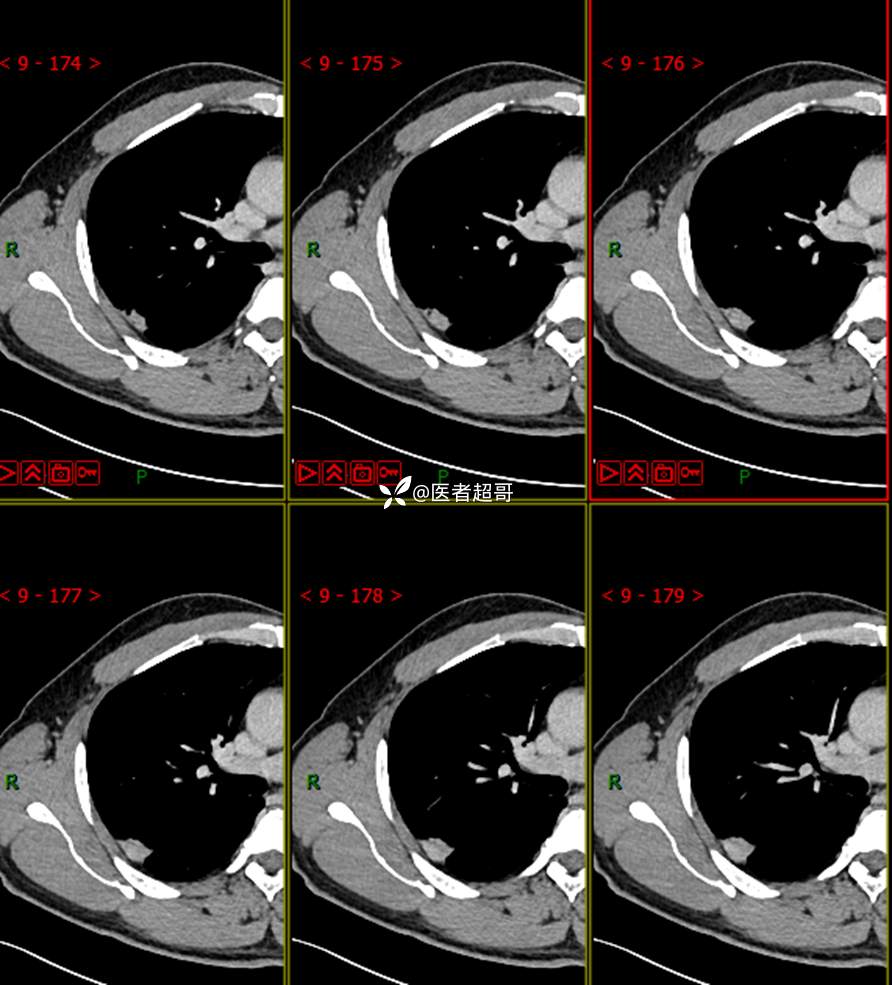

现病史:患者1年余前于体健中心行胸部X片发现右上肺叶密度增高影,无明显咳嗽,咳痰,无痰中带血及咯血,无胸痛及胸闷、气短,无发热、盗汗及全身乏力。无头痛、头晕,无腹痛、腹胀及恶心、呕吐,无声音嘶哑及呛咳,未行特殊治疗。后患者定期复查胸部CT,未见明显变化。2023-2-6患者于我院复查胸部CT:右肺上叶、下叶交接处胸膜下见实性结节影,最大截面约2.6cm×1.4cm,较前增大,建议行手术治疗。今为求进一步诊治,遂来我院就诊,门诊以“肺肿物”收入我院,患者自发病以来,神志清,精神可,饮食可,睡眠良好,大小便正常,近期体重未见明显增减。